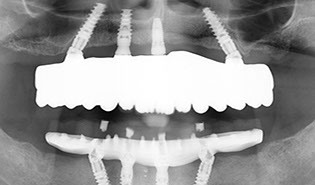

3.2 Immediate Load Prosthetics (All-on-4)

This part of the course covers the methods of diagnosis, practical treatment planning, pre-surgical prosthodontics, imaging, armamentarium, and clinical techniques needed for this exciting treatment modality. Crucial to this treatment modality is the understanding of the biomechanical aspects and functional loading of the immediate full arch prostheses. The aesthetic and phonetic requirements, space requirements, laboratory communication, insertion techniques post-operative follow-up and hygiene requirements are key to this treatment.

Tilted implants - biomechanical aspects and survival rates

Cantilevers

Treatment planning - pre- and postoperative radiographic

examinations and 3D imaging